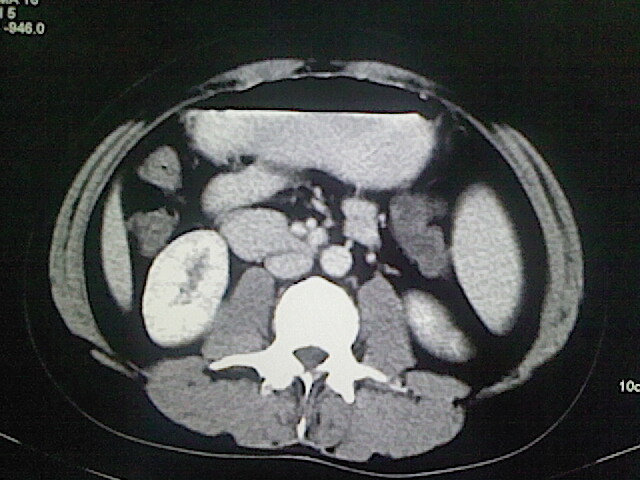

以下是引用卜一在2009-3-14 9:49:00的发言:[br]胆囊萎缩,胆囊壁不规则增厚,内部结构模糊,增强明显强化。另:肝左叶外侧段肝囊肿。支持:慢性胆囊炎!高度可疑:胆囊癌!

以下是引用余辉在2009-3-14 8:48:00的发言:[br]1)慢性胆囊炎。2)肝左叶外侧段肝囊肿。3)脂肪肝。[br]支持,胆囊萎缩,密度增高,不知b超具体有何提示,钙胆汁?结石?

以下是引用jiangjing在2009-3-14 10:18:00的发言:[br]1)慢性胆囊炎。2)肝左叶外侧段肝囊肿。3)脂肪肝。4.】建议行肝功能检查